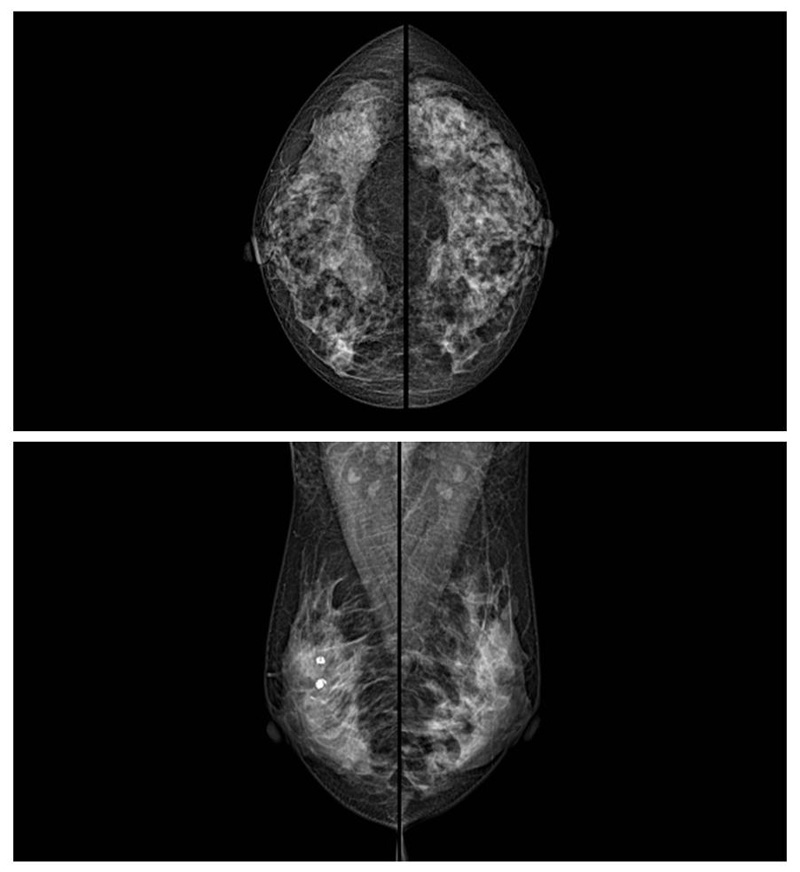

乳腺癌的發生率越來越高,已經是我們國家的癌癥之一已成為女性健康“頭號殺手”。乳腺DR可提高乳腺癌早期檢出率并精準定位。發現和診斷早期乳腺癌最有效的方法之一,明顯利大于弊女性都要重視乳腺的檢查。輻射很小最簡便、最可靠、無創性檢查手段,做一次乳腺DR的劑量相當于7周的正常生活。尤其是對于40歲以上的女性尤為重要,那么乳腺DR是怎么進行檢查的呢?我們來了解一下,為廣大朋友在檢查前有點心理準備。檢查時候是避開經期的前后,月經來后的7天左右比較合適。需要脫衣服檢查,根據拍片的擺位要求,有頭尾位置,內外斜位,還有側位。定點放大壓迫方法可以更細微清晰的檢查出病灶。

對乳房進行按壓,這樣才能得到檢查的好效果,按壓大概60秒左右,做好心理準備不可以過度緊張有點疼痛感覺,這樣不會抖動影響了檢查的效果。減少患者壓迫時間和輻射劑量??蛇_到最高極限分辨率10.1 lp/mm,可實現高清成像,提高微小病變檢出率??梢园l現乳腺增生,各種良惡性腫廇通過三維斷層掃描,提高乳腺微小癌灶的檢出率和早期乳腺疾病特別是乳腺癌的診斷率。通過特殊的支架,加大膠片與物體之間的距離來獲取更多的影像信息。